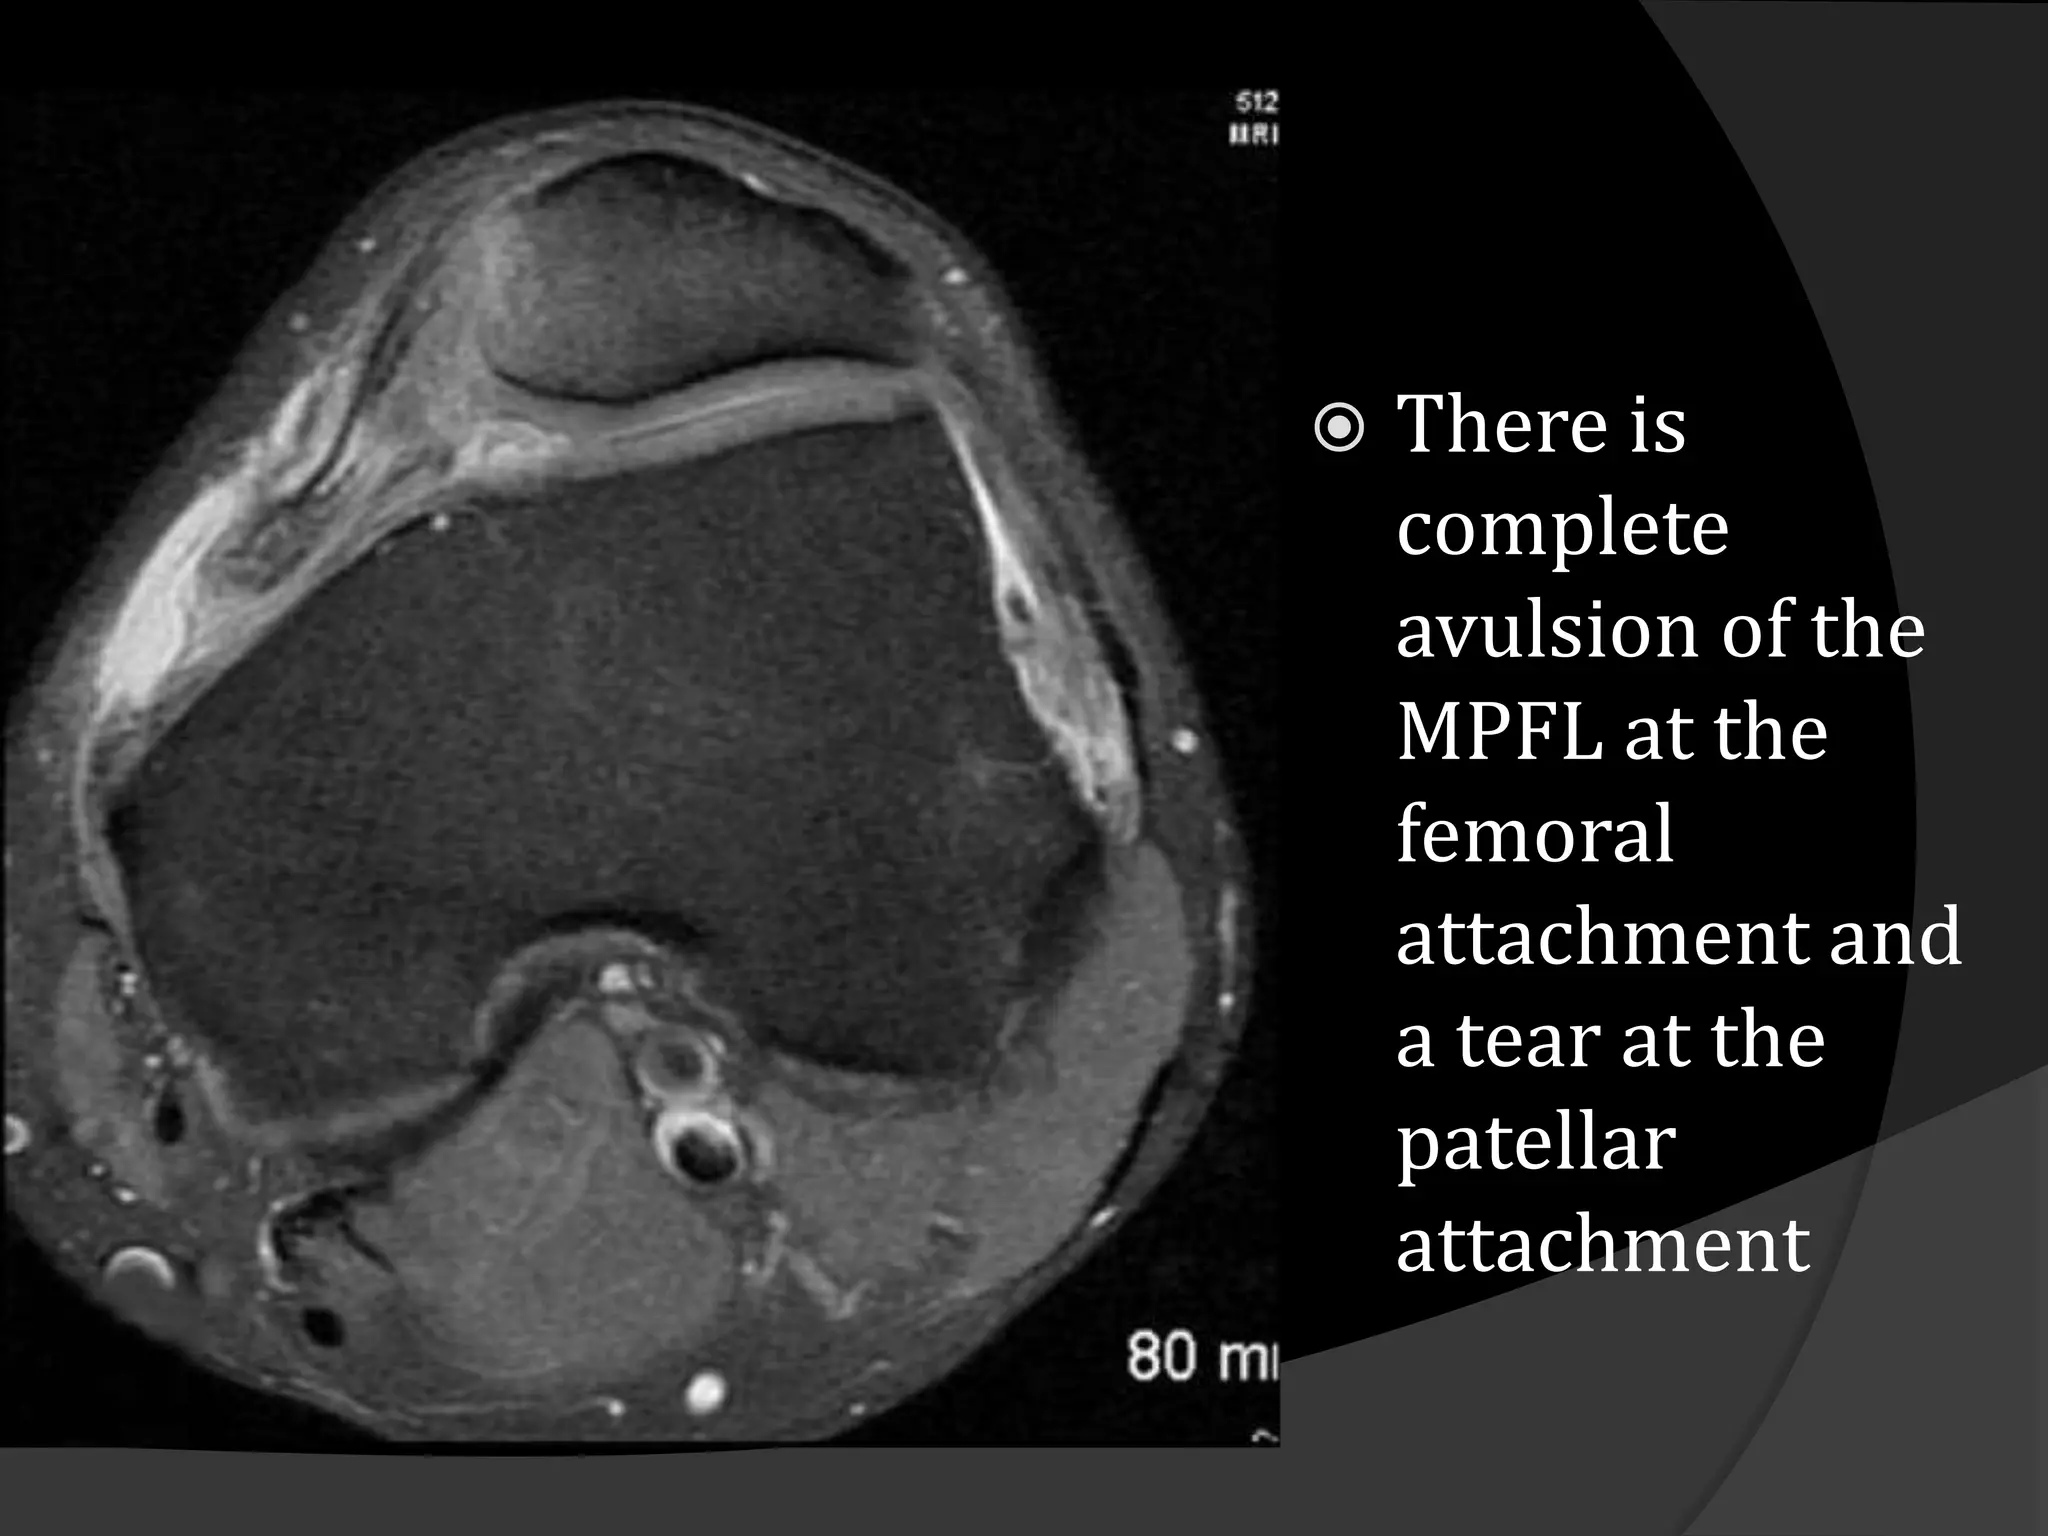

   There is

complete

avulsion of the

MPFL at the

femoral

attachment and

a tear at the

patellar

attachment

There is complete avulsion of the MPFL at the femoral attachment and a tear at the patellar attachment